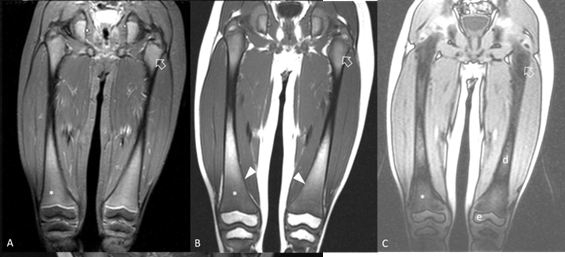

2). Lower femoral MRI revealed abnormal bone marrow signal for age with

mild Erlenmeyer deformity, suggestive of Gaucher disease (Figure 3).

Figure 3:

MRI scan of

femurs, coronal plane. A. STIR sequence, shows intermediate signal intensity at

proximal (arrow) and distal (*) femoral metaphyses which would be expected only

for proximal metaphyses at this age. B. T1-w sequence shows areas of

hypointense bone marrow. There is minimal widening of distal femoral metaphyses

consistent of Erlenmeyer flask deformity (arrowheads). C. Chemical shift

opposed-phase image, confirms signal drop at areas of normal red bone marrow

(arrow) and lack of signal drop at infiltrated metaphyses (*) and at areas of

fatty marrow at epiphyses (e) and diaphyses (d).